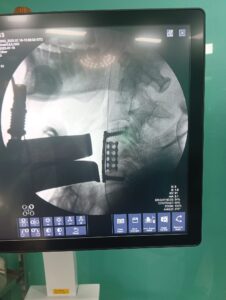

Another Paralysis Prevented by Successful Cervical Spine Surgery in Indore Read More May 28, 2024 8:08 am

A Remarkable Success: Lumbar Spine Stenosis Surgery on a 68-Year-Old Patient with Multiple Comorbidities Read More May 24, 2024 12:09 pm